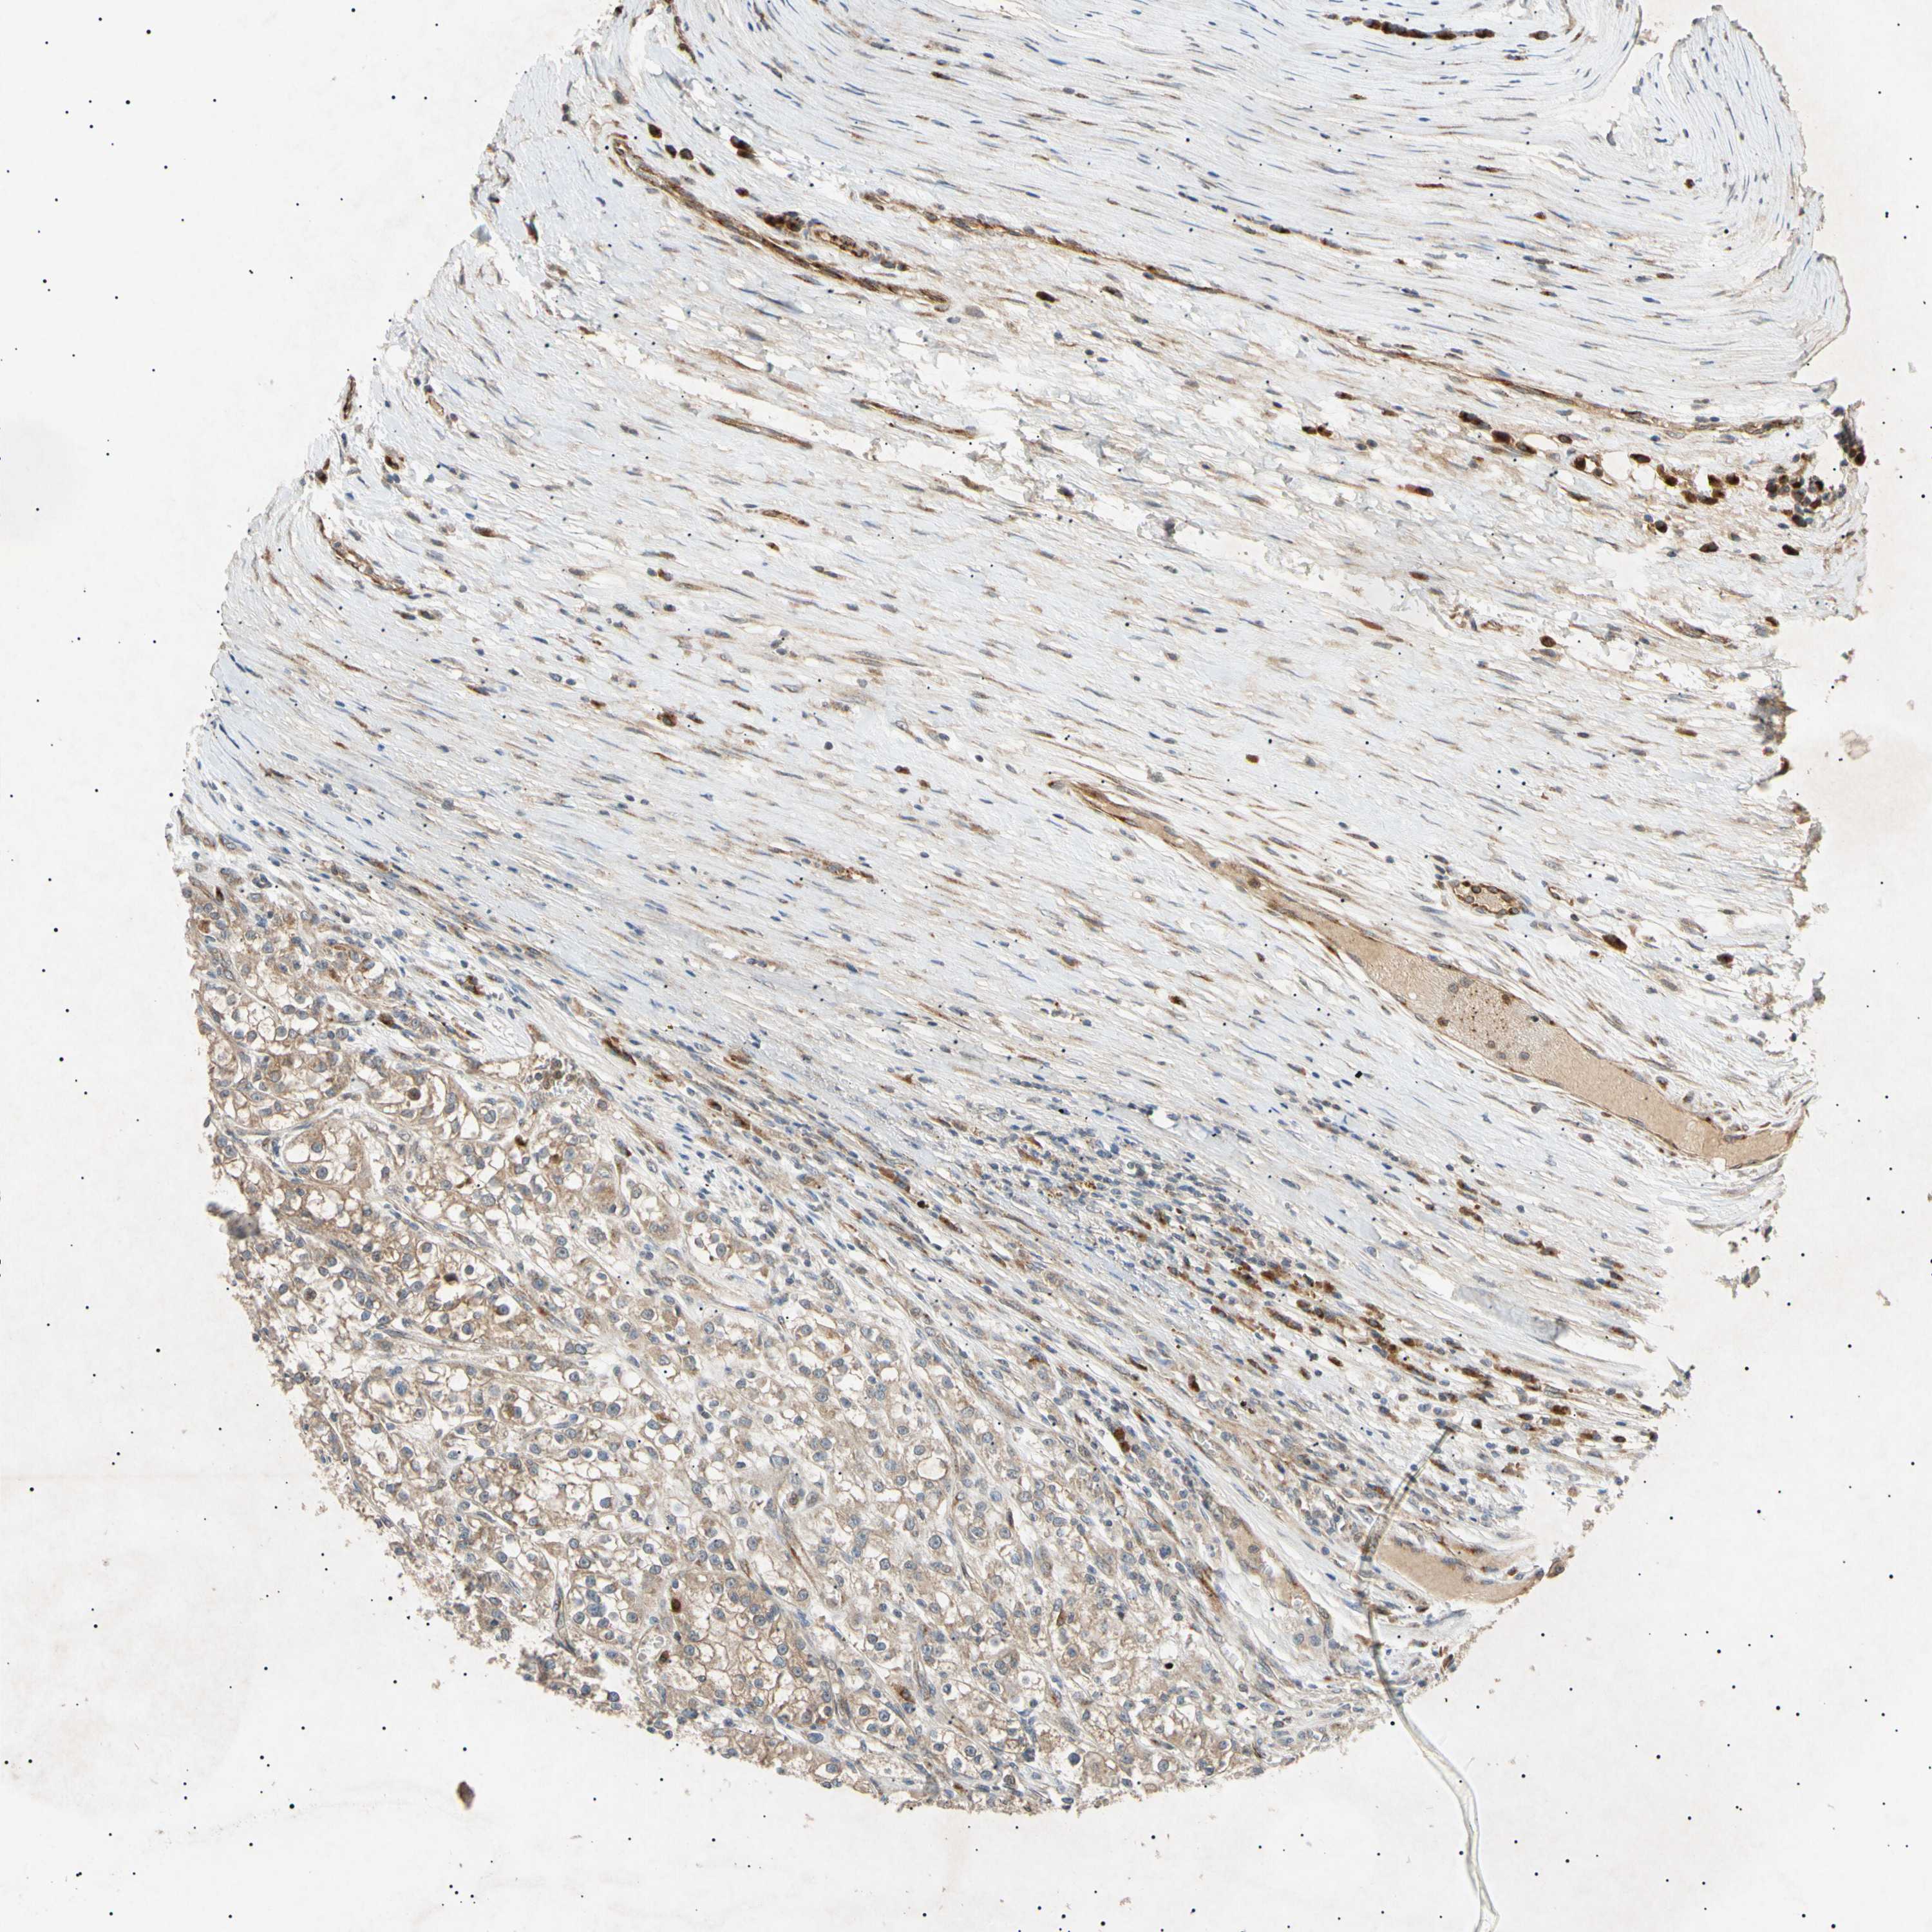

KIDNEY RENAL CLEAR CELL CARCINOMA (TCGA) - Interactive survival scatter ploti

The Survival Scatter plot shows the clinical status (i.e. dead or alive) for all individuals in the patient cohort, based on the same data that underlies the corresponding Kaplan-Meier plots. Patients that are alive at last time for follow-up are shown in blue and patients who have died during the study are shown in red.

The x-axis shows the expression levels (FPKM) of the investigated gene in the tumor tissue at the time of diagnosis. The y-axis shows the follow-up time after diagnosis (years). Both axes are complimented with kernel density curves demonstrating the data density over the axes. The top density plot shows the expression levels (FPKM) distribution among dead (red) and alive patients (blue). The right density plot shows the data density of the survived years of dead patients with high and low expression levels respectively, stratified using the cutoff indicated by the vertical dashed line through the Survival Scatter plot. This cutoff is automatically defined based on the FPKM cutoff that minimizes the p-score. The cutoff can be changed by dragging the vertical line or by entering a cutoff value in the square labeled "Current cut-off".

Under the Survival Scatter plot the p-score landscape (black curve; left axis) is shown together with dead median separation (red curve; right axis). Dead median separation is the difference in median mRNA expression between patients who have died with high and low expression, respectively. It is calculated as follows: median FPKM expression of dead patients with high expression - median FPKM expression of dead patients with low expression. This is intended to aid the user in visually exploring custom cutoffs and the associated p-scores and dead median separation.

Individual patient data is displayed and can be filtered by clicking on one or more of the category buttons on the top of the page. Categories describing expression level and patient information include: high, low, alive, dead, female, male and tumor stages. The scale of the x-axis can be toggled between linear and log-scale by clicking on the "x log" button. Mouse-over function shows TCGA ID, patient information and mRNA expression (FPKM) for each patient.

& Survival analysisi

Kaplan-Meier plots summarize results from analysis of correlation between mRNA expression level and patient survival. Patients were divided based on level of expression into one of the two groups "low" (under cut off) or "high" (over cut off). X-axis shows time for survival (years) and y-axis shows the probability of survival, where 1.0 corresponds to 100 percent.

TUBB4A is not prognostic in Kidney Renal Clear Cell Carcinoma (TCGA)

Best expression cut offi

Based on the FPKM value of each gene, patients were classified into two groups and association between prognosis (survival) and gene expression (FPKM) was examined. The best expression cut-off refers the FPKM value that yields maximal difference with regard to survival between the two groups at the lowest log-rank P-value. Best expression cut-off was selected based on survival analysis .

When clicking on this number, the vertical dashed line indicating cut-off, the interactive survival plot, and the Kaplan-Meier curve will be adjusted to show results based on the best expression cut-off.

: 8.26

TCGA RNA samplesi

RNA-seq data is reported as average FPKM (number Fragments Per Kilobase of exon per Million reads), generated by the The Cancer Genome Atlas (TCGA) .

Normal distribution across the dataset is visualized with box plots, shown as median and 25th and 75th percentiles. Points are displayed as outliers if they are above or below 1.5 times the interquartile range. FPKM values of the individual samples are presented next to the box plot.

Average pTPM 8.6

Number of samples 521